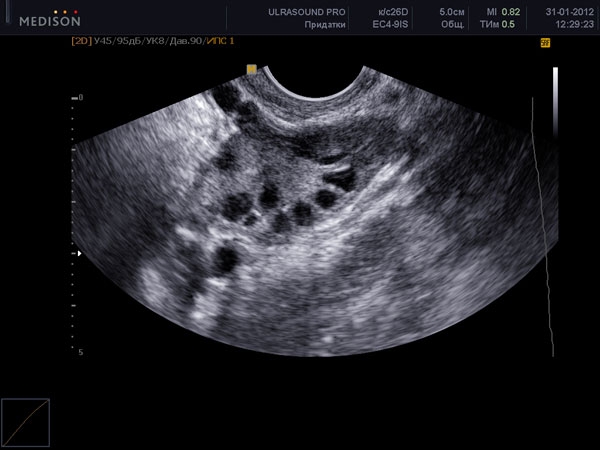

Срок беременности врачи начинают отсчитывать не с момента зачатия, а с первого дня последней менструации. Таким образом, первая неделя беременности на самом деле не является периодом беременности, а представляет собой активную подготовку организма к этому важному этапу. На УЗИ в это время можно заметить, что маточная полость немного увеличена, так как в ней накапливаются менструальная кровь и отмершие клетки эндометрия. Также можно увидеть мелкие антральные фолликулы. В этот период в организме женщины наблюдается естественное снижение уровня гормона эстрогена, что приводит к тому, что фолликулостимулирующий гормон (ФГС) «стимулирует» созревание нескольких фолликулов.